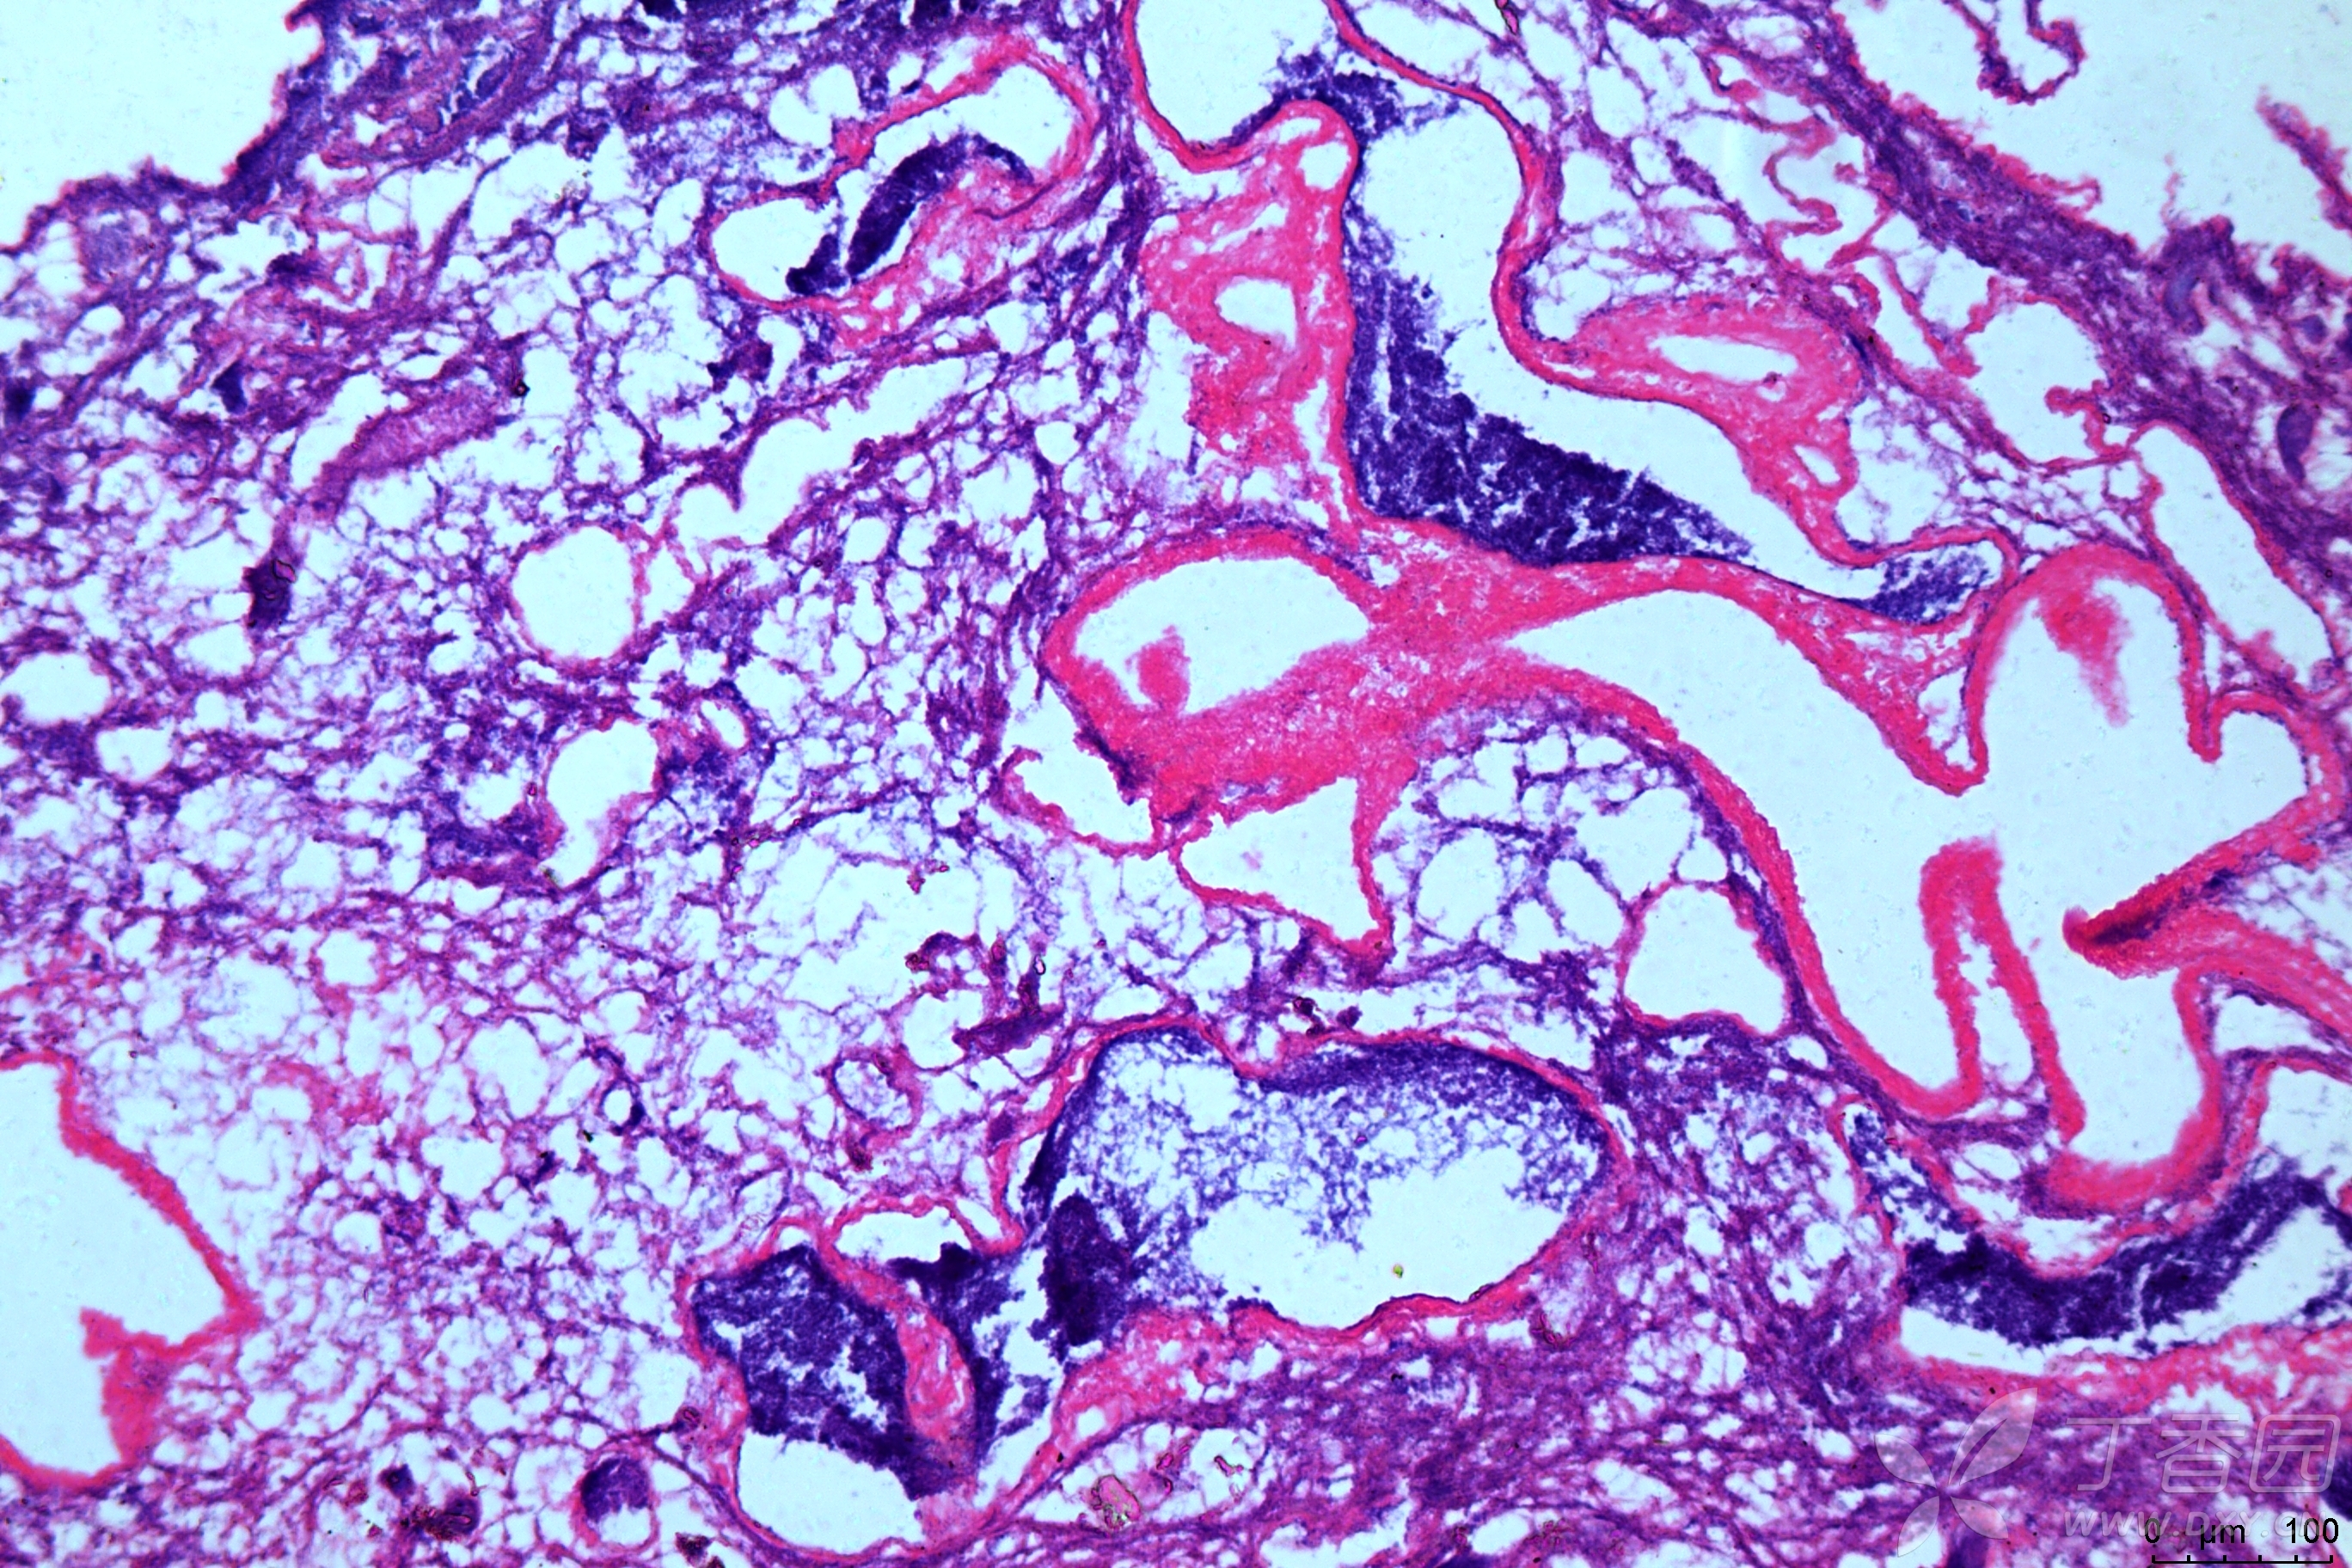

请问he染色后,肝组织中的大团的紫色是什么,是聚集在一起的细胞团吗?

图片尺寸2736x1824